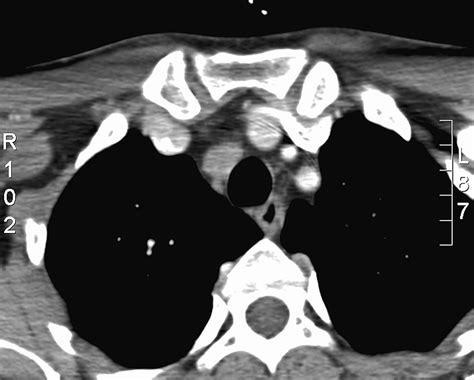

Imaging Studies: Imaging studies, such as ultrasound, computed tomography (CT), and magnetic resonance imaging (MRI), can provide detailed images of the paratracheal lymph nodes. These studies can help determine the size, shape, and location of the nodes, as well as any abnormalities or signs of metastasis.

| CT Scan | Provides detailed images of the nodes and surrounding structures | Exposes the patient to radiation |